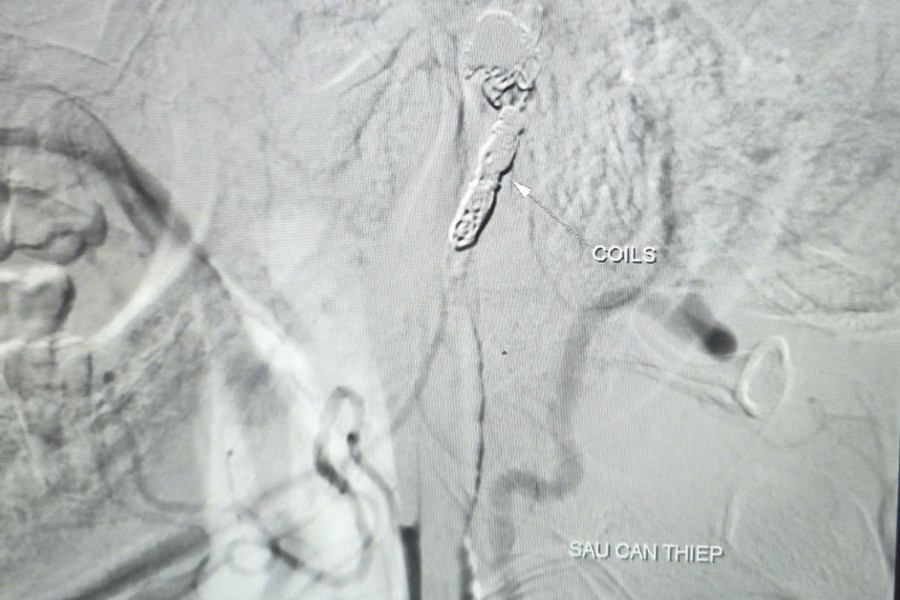

vom-hau-2.jpg

Không còn hình ảnh thoát mạch sau can thiệp. Ảnh: BVCC.

Các bác sĩ đã tiến hành bóng chẹn dòng chảy để kiểm soát lượng máu từ túi phình, sau đó luồn vi ống thông chọn lọc đến vị trí tổn thương và thả 9 vòng xoắn kim loại (coils) nhằm gây tắc hoàn toàn ổ giả phình và động mạch cảnh trong phải, kiểm soát triệt để nguồn chảy máu.

Chụp kiểm tra từ động mạch cảnh trong trái cho thấy có tuần hoàn bàng hệ nuôi bán cầu não phải qua động mạch thông trước, đảm bảo tưới máu não sau can thiệp. Toàn bộ quá trình can thiệp kéo dài khoảng 90 phút.